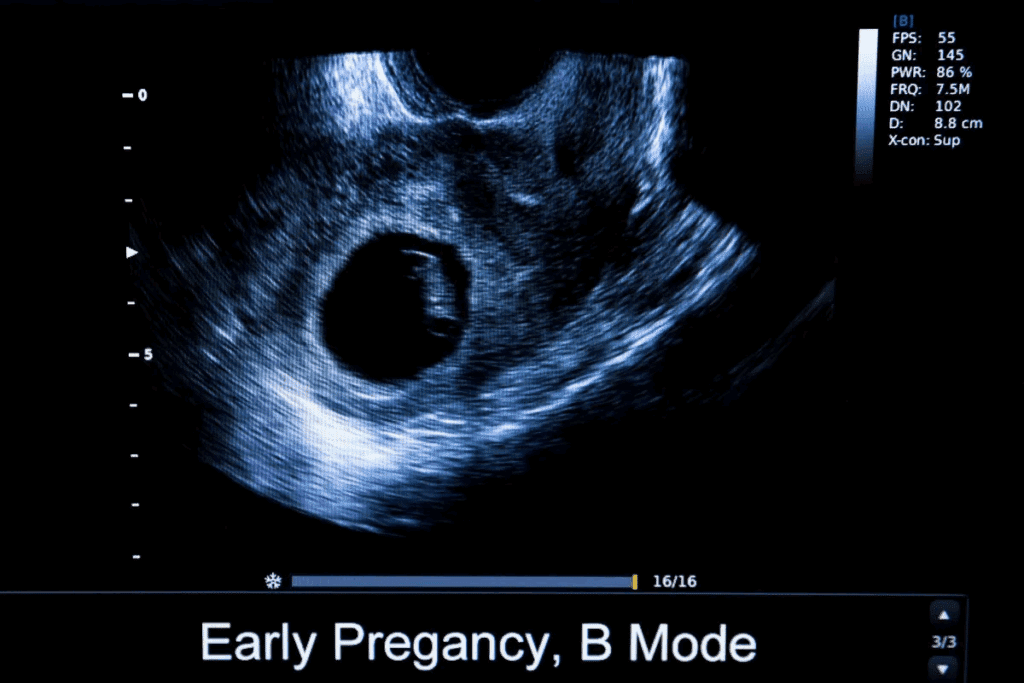

Transvaginal Ultrasound as the Gold Standard

Transvaginal ultrasound is the top tool for finding ectopic pregnancies. It involves putting an ultrasound probe in the vagina. This gives a clear view of the reproductive organs. Transvaginal ultrasound helps spot pregnancy early and where it is, which is vital for diagnosing ectopic pregnancies.

What Doctors Can See at 5-6 Weeks

At 5-6 weeks, doctors can see the gestational sac and where it is with transvaginal ultrasound. In normal pregnancies, the sac is in the uterus. But in ectopic pregnancies, it’s outside, often in the fallopian tube. Early visualization is key for quick action.

Empty Uterus Signs and Other Ultrasound Indicators

One important sign of an ectopic pregnancy on ultrasound is an empty uterus. No gestational sac is seen inside the uterus. Other signs include a pseudogestational sac, free fluid in the pelvis, or an adnexal mass. These signs, along with symptoms and hCG levels, help confirm an ectopic pregnancy.